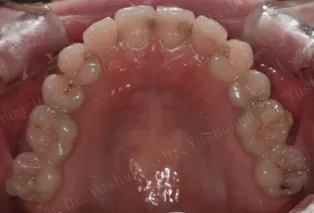

Intraoral photos